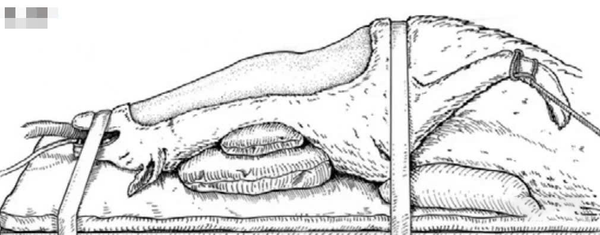

Để đảm bảo tiếp cận cột sống cổ qua đường bụng, cổ cần được cố định thẳng. Túi cát hoặc khăn được đặt dọc theo phía sau cổ để duy trì tư thế kéo dài tối đa, đồng thời hạn chế rung lắc hoặc xoay sang hai bên. Điều này giúp mở rộng không gian thao tác, tạo điều kiện thuận lợi cho việc tiếp cận và thực hiện phẫu thuật.